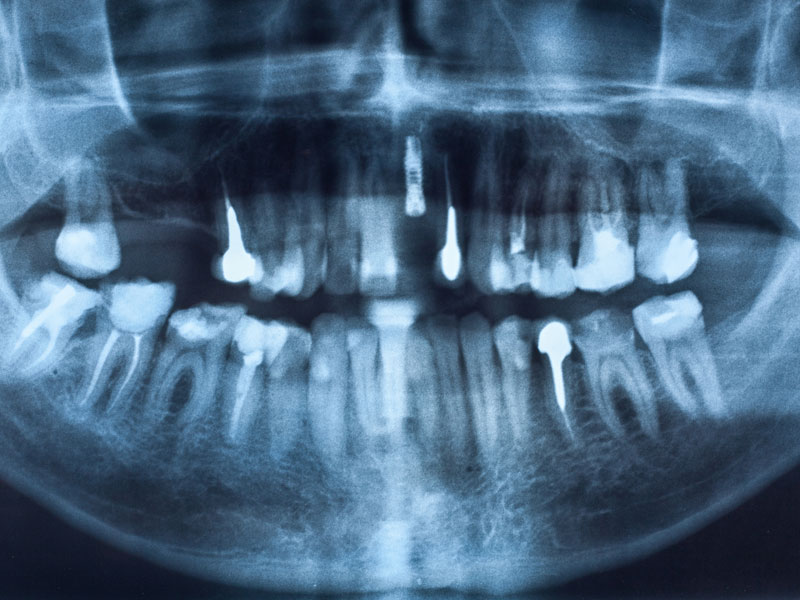

Out of court settlement of $100,000.00 policy limit for woman following 32 year course of periodontal neglect in case against Florida general dentist. Plaintiff was a 55 year old school teacher who had been under the almost continuous care of her general dentist from 1963 until 1995. During her 32 year course of treatment by...Read More